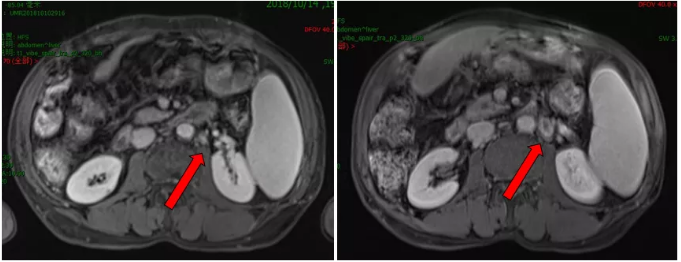

2019.08.18 MRI示腹膜后一增大淋巴结,约2.2cm×1.3cm,DWI弥散受限,环形强化,较前增大,考虑淋巴结转移。

影像学检查

2018.08.19患者现仅腹膜后淋巴结出现进展,其他部位稳定,建议全身治疗不变,行腹膜后淋巴结放疗。

2019.08.26-2019.09.06予以行腹膜后淋巴结姑息放疗45GY/25f。